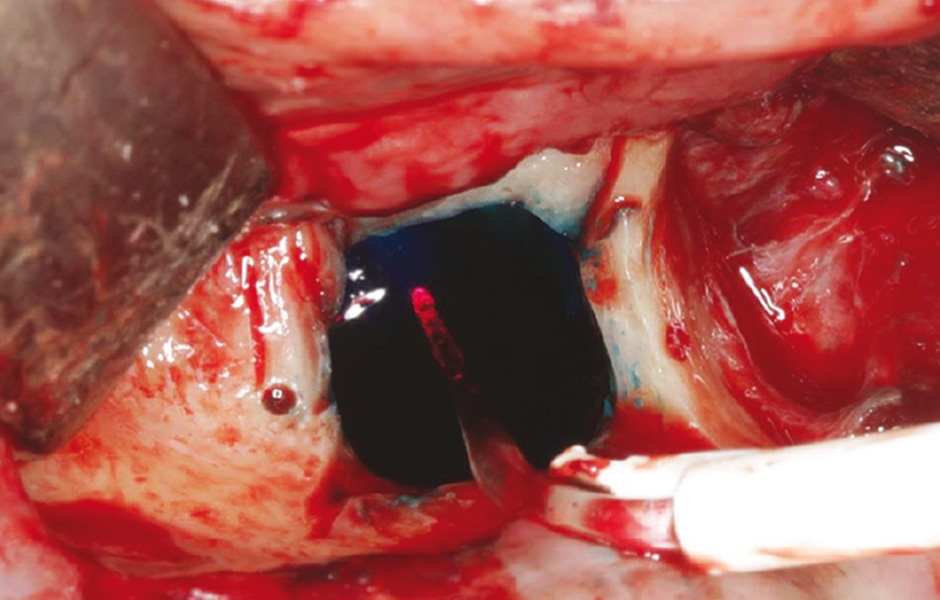

Do studie bylo zařazeno 10 pacientů s aspergilózou maxilárního sinu. U všech pacientů byl na panoramatických snímcích i na CBCT patrný radiopakní stín. CBCT navíc ukázalo, že čelistní dutina byla kompletně vyplněna homogenní patologickou masou. Chirurgická léčba sinu byla provedena za antibiotické profylaxe (Amoxicillin 2 g/den po dobu 7 dní) a intravenózní sedace (Midazolam). Kostní okénko bylo vytvořeno mikropilkou (DENTSPLY Implants), umožnilo bezpečný přístup do sinu. Po odklopení separovaného kostního fragmentu byla aspergilóza spolu s cizorodým materiálem kompletně odstraněna a dutina vypláchnuta peroxidem vodíku (H₂O₂ 3 %). Pro dodatečnou dezinfekci byla použita fotodynamická dekontaminace laserem HELBO (HELBO, Bredent Medical GmbH). Na závěr zákroku byla kostěná lamela vrácena zpět jako biologický uzávěr sinu a fixována resorbovatelnými stehy. Histopatologické vyšetření ve všech případech potvrdilo infekci aspergilózou. Po třech měsících, kdy CBCT potvrdilo nepřítomnost sinusové patologie a průchodné ostium, byla provedena augmentace kosti. Kostní bloky byly odebrány z retromolárové oblasti mandibuly a přeneseny ve 3D konfiguraci podle split-bone block techniky v kombinaci se sinus liftem. Sinus byl augmentován autologní kostí a biomateriálem (FRIOS Algipore®, DENTSPLY Implants) vrstvenou technikou. Po dalších třech měsících byly do augmentované oblasti zavedeny implantáty. O další tři měsíce později byly implantáty odhaleny a následně byla zhotovena definitivní protetická náhrada.“

Obr. 3: Po vyjmutí kostěné lamely byla patrná zelenošedá masa; histologie potvrdila aspergilom.

Obr. 4: Po debridementu provedena fotodynamická dekontaminace laserem HELBO.